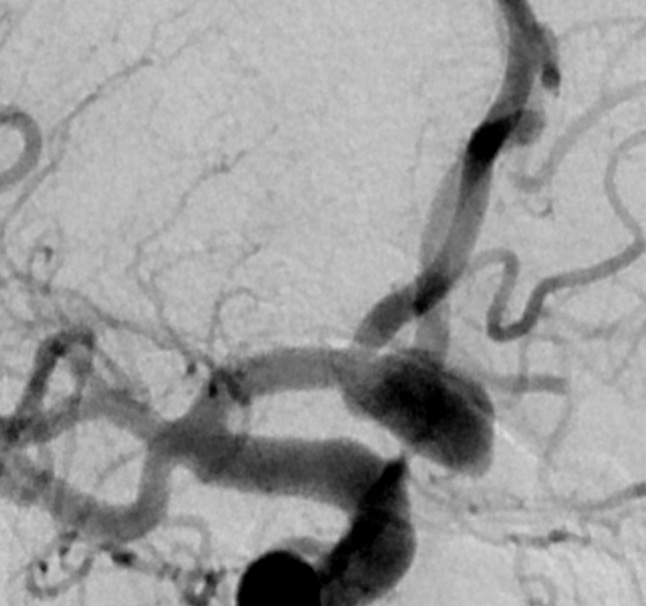

Klinische Anwendung des ACCERO® heal Stents

Nach der Freisetzung

Nach der Behandlung